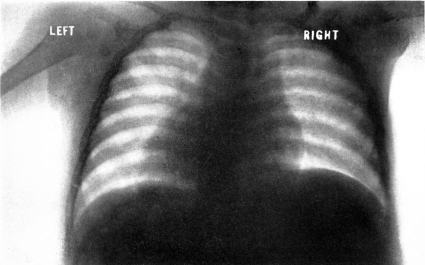

| 19. | Scorbutic beading of ribs. Roentgenogram | 198 |

| 21. | Cardiac enlargement. Roentgenogram | 200 |